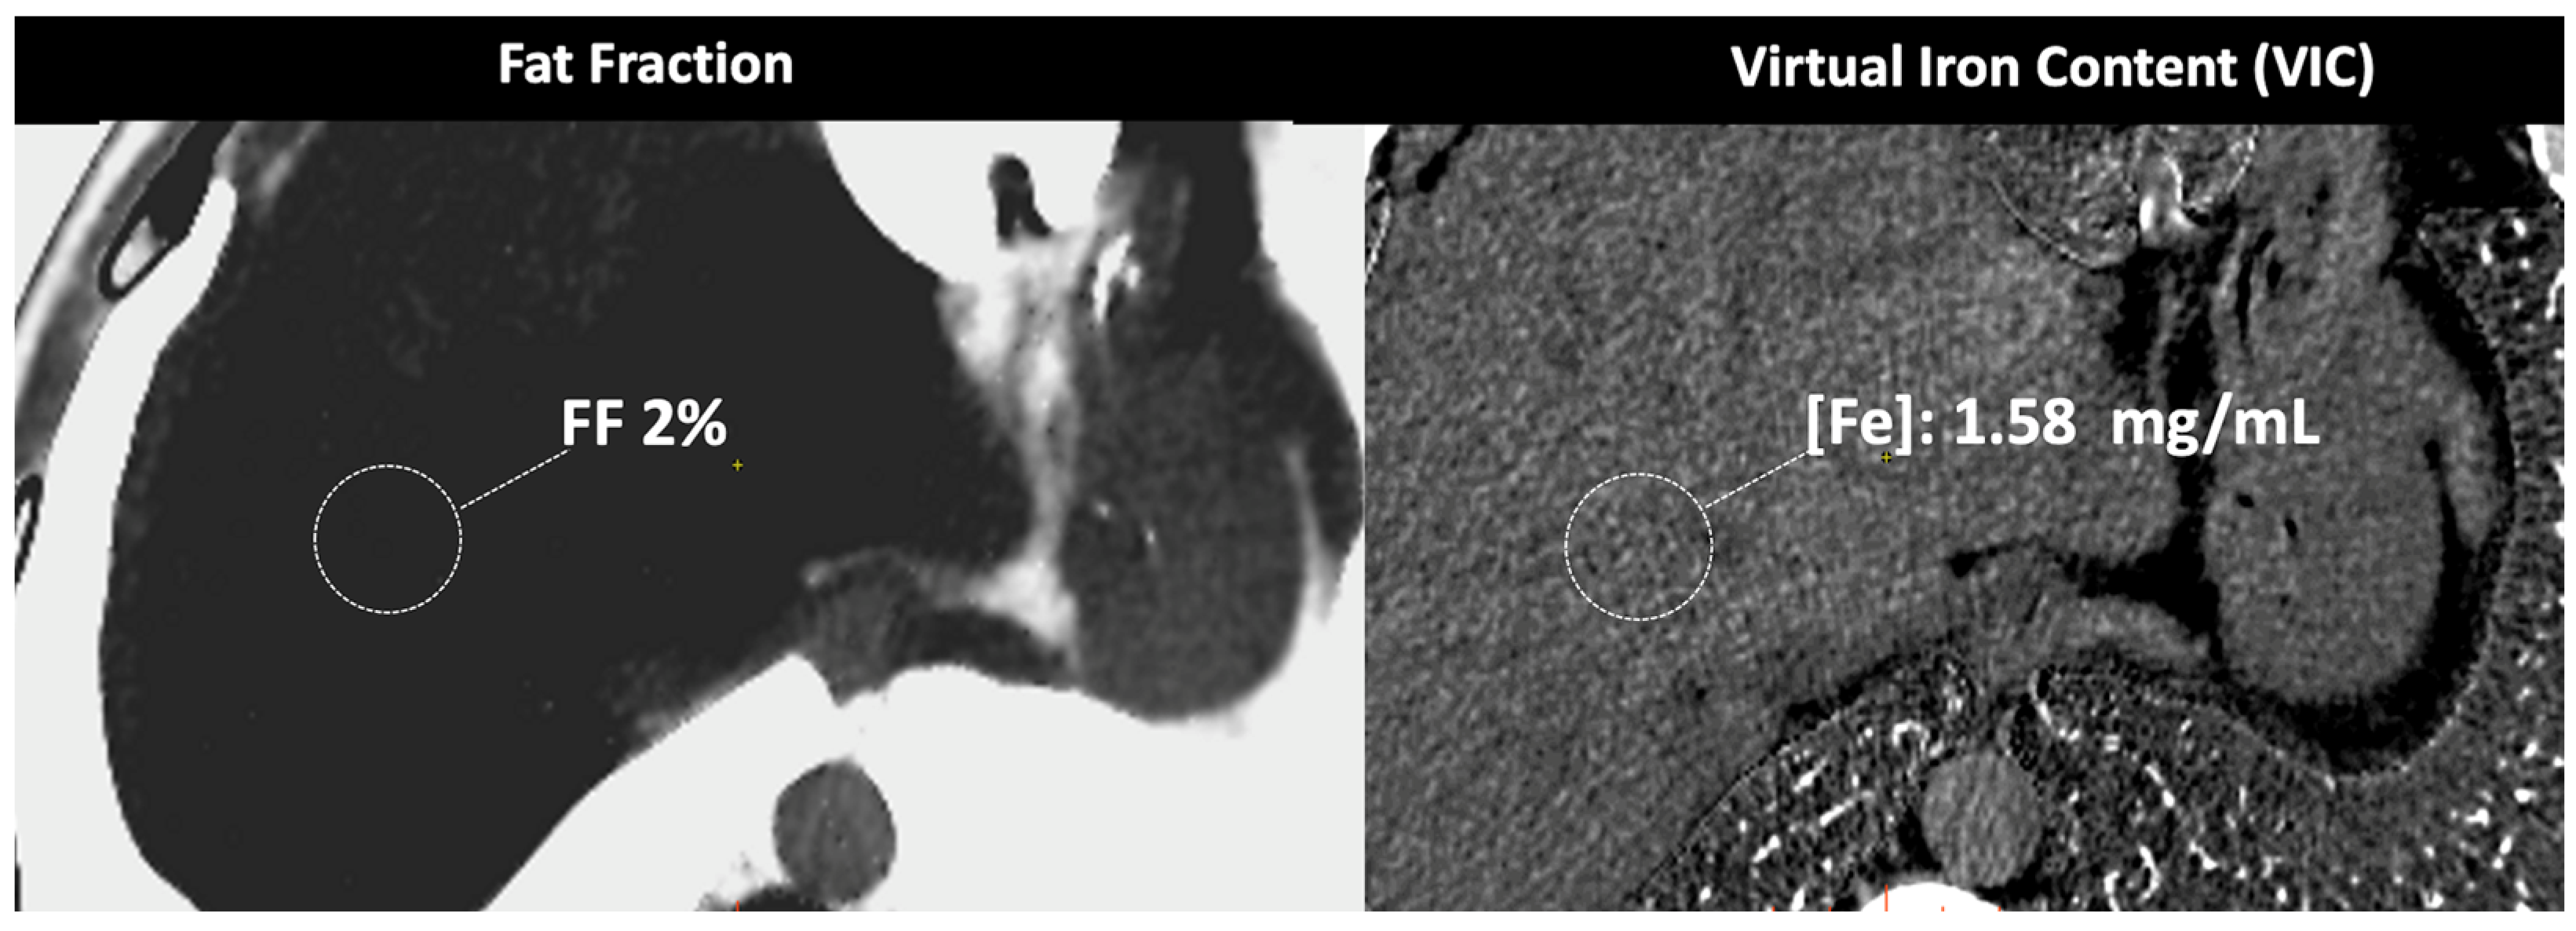

- In the case of adrenal imaging, the fat fraction has higher sensitivity than VUE attenuation and the traditional threshold of 10 HU or lower for diagnosing adrenal adenomas. Loonis et al. [20] reported a fat fraction threshold of ≥23.8% with 100% specificity and 59% sensitivity (Figure 11). Furthermore, DECT-derived parameters can be used to differentiate adrenal adenoma from pheochromocytoma, or metastases based on the effect of lipid components on attenuation [33,34]. Finally, the iodine concentration can also be an imaging marker of dominant adrenal lesions in functional syndromes [35].

- DECT-derived fat fraction, a quantitative marker of fat content in the liver, correlates with histopathological examination, the reference standard for steatosis. Pathology assessment is based on the fraction of hepatocytes containing fatty vesicles: grade 0 (healthy, <5%), grade 1 (mild, 5–33%), grade 2 (moderate, 34–66%), and grade 3 (severe, >66%), while DECT evidences a substantially lower fatty liver content due to the simultaneous presence of fat, water, and soft tissue in the voxel. Pathologic data can be correlated with DECT-derived fat quantification and a conversion factor may aid in the prediction of the histopathological fat fraction based on fat quantification using DECT [30]. Patients with co-existing hepatic fat and iron overload represent a clinical challenge. In the presence of multiple material elements in the same voxel, it is still not clear whether the presence of fat and iron in the same voxel results in reduced performance of DECT [27].